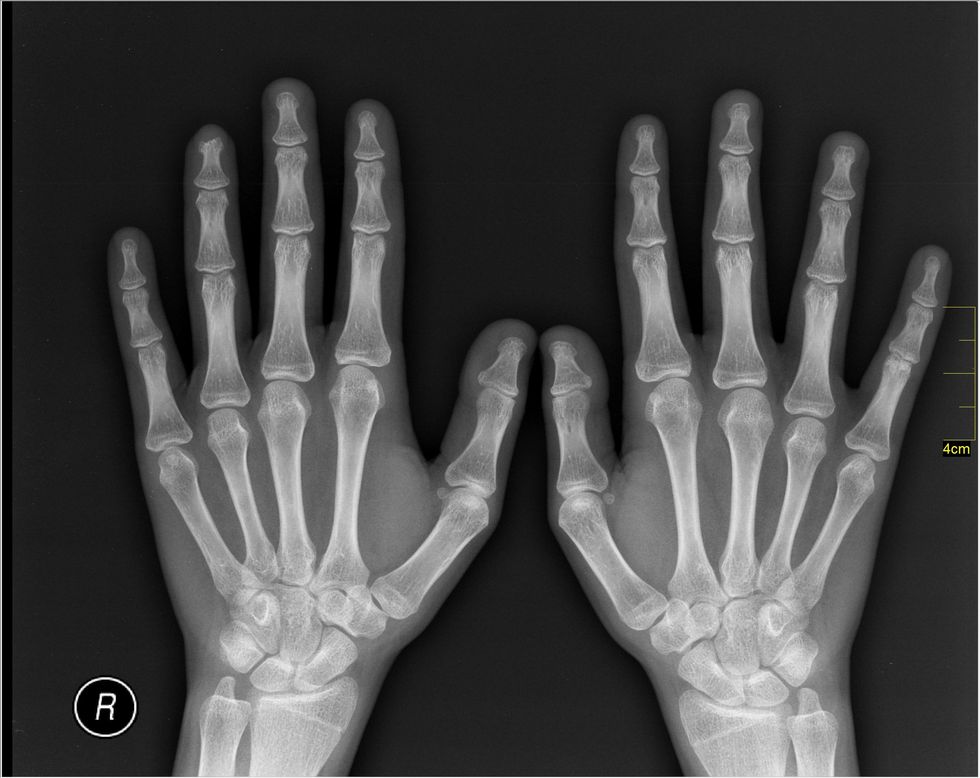

For those of you who don't know, I broke my wrist and tore a ligament about 2 weeks ago. I'm in a cast that starts at my knuckles and ends right before my elbow. It's hard to miss, so it starts conversations with random people all over. Of course, this leads to curious questions and stores about their injuries or someone they know's injury.